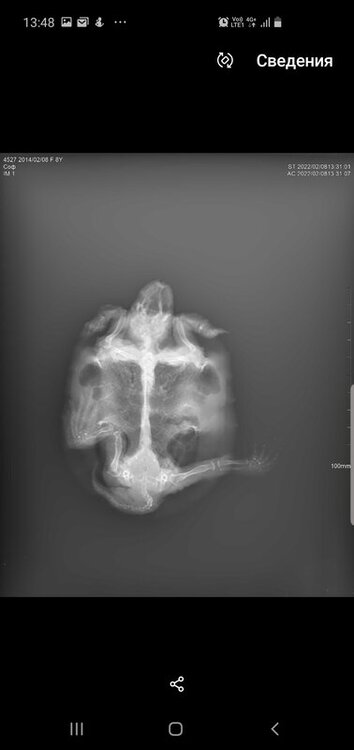

Консультанты moth Ваше имя: Мария Локация: Москва Опубликовано: 8 февраля 2022 Консультанты Опубликовано: 8 февраля 2022 @Зюлиф нет, к сожалению я в снимках могу только что-то простое увидеть - газы или яйца или инородное тело. У Вас всё сложно из-за деформации панциря.

Зюлиф Ваше имя: Софа Локация: Набережные Челны Опубликовано: 8 февраля 2022 Автор Опубликовано: 8 февраля 2022 1 час назад, moth сказал: @Зюлиф нет, к сожалению я в снимках могу только что-то простое увидеть - газы или яйца или инородное тело. У Вас всё сложно из-за деформации панциря. Все же прикреплю пару фото.И вопрос:сегодня доставили уф лампу simple zoi bulk UVB10.0 13W,на каком расстоянии вешать ее от островка,подскажите, пожалуйста

Консультанты moth Ваше имя: Мария Локация: Москва Опубликовано: 8 февраля 2022 Консультанты Опубликовано: 8 февраля 2022 @Зюлиф я тут вижу только, что лёгкие мутные, но это могут и органы перекрывать. Я понимаю, что ожидание ответа может быть некомфортным, но это в реальности быстрее очных приёмов тех же самых, на них может быть запись и неделю-две.

Консультанты moth Ваше имя: Мария Локация: Москва Опубликовано: 10 февраля 2022 Консультанты Опубликовано: 10 февраля 2022 @Зюлиф как нету, в 2.35 она Вам написала, посмотрите телеграмм По поводу рентгена: - Объем легких незначительно снижен - Есть признаки скопления экссудата (жидкости), что может говорить как раз о пневмонии. - Плотность костных структур снижена, неравномерная. а дальше как раз про лечение и антибиотик